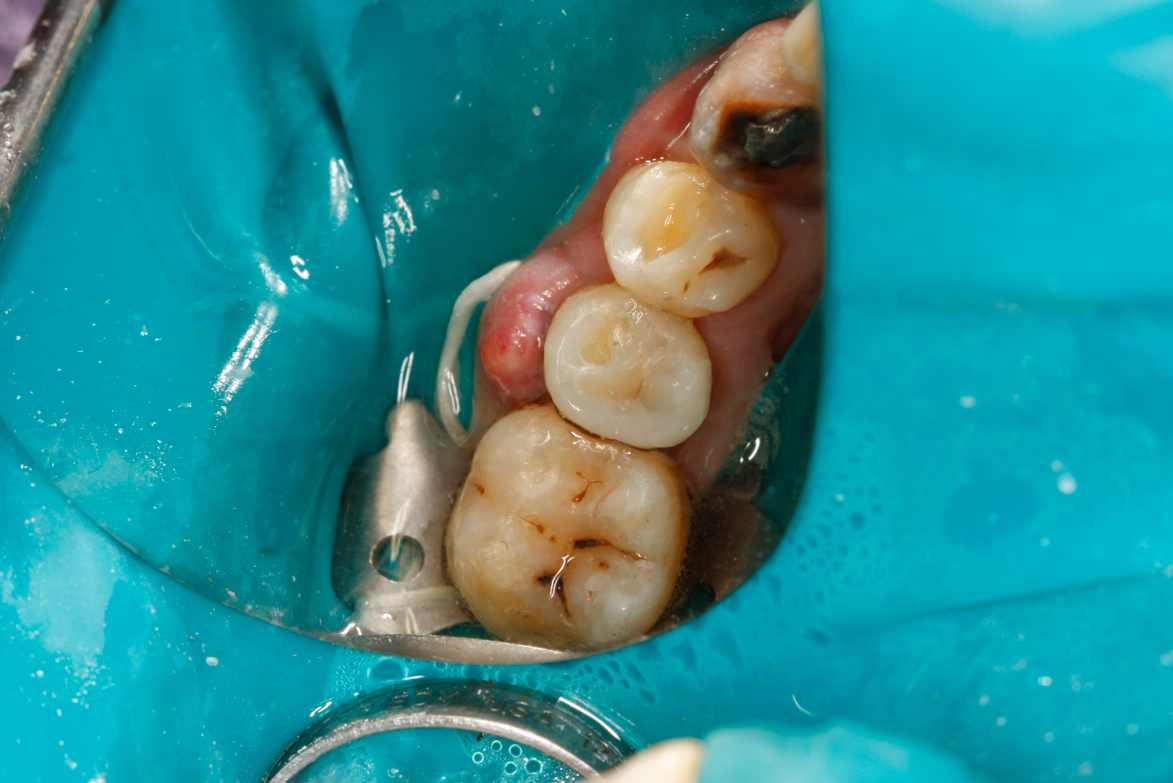

A deep distal occlusal preparation was performed and a matrix band (Paraband, Practicon) was placed again, such that no wedge needed to be placed (Figure 32). The Groman Etchmaster was utilized to remove biofilm as previously shown in Figure 12. A total etch technique with 37% phosphoric acid was employed (Figure 33), and after thorough rinse and damp dry, a universal adhesive (Scotchbond Universal, 3M) with MDP was applied and light-cured 40 seconds at 1,200 mw/cm2 due to the depth of the box form (Fig- ure 34). Figure 35 shows the dual-cure bulk-fill flowable composite (Bulk EZ Plus, Zest Dental Solutions) being injected into the deep box with a 20-gauge bendable needle. It is important to keep extrusion pressure on the plunger while withdrawing the needle to prevent bubbles or voids in the composite interface with the tooth structure. Overfilling by approximately 10% and smoothing the surface only with brushes promotes good marginal seal (Fig- ure 36). It is critical to not disturb the occlusal surface of any dual-cure bulk-fill flowable with an attempt to "soft sculpt," as that may create marginal voids.

Fig 32. Preparation is completed, caries are removed, sand blasting with potassium carbonate is performed, and matrix band is placed.

Figure 32

Fig 33. Total etch with 37% phosphoric acid is performed.

Figure 33

Fig 34. Universal adhesive is applied in total etch technique and is light-cured for 40 seconds due to depth of cavity.

Figure 34

Fig 35. Injection filling of cavity preparation with dual-cure bulk-fill flowable composite to a slight overfill.

Figure 35

Fig 36. Injection overfill smoothed with a brush. At this step, it is important not to disturb the margins.

Figure 36